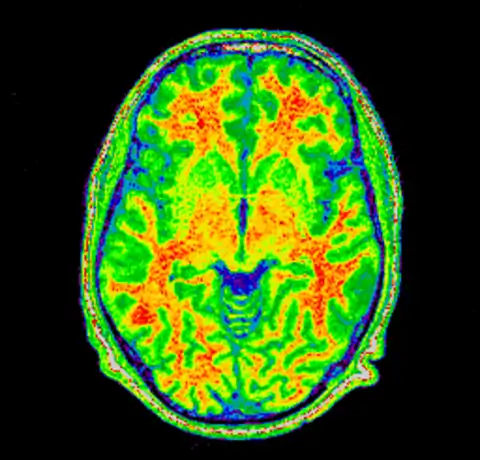

And then produce an image of it using the Spectral colormap

mincpik -scale 2 field.mnc -slice 150 -lookup -spectral field.png

And then for completeness sake, here are the original and corrected image using a spectral colormap to better visualise the change. Note that in the second (corrected) image the intensity of the white matter is more uniform (the red part).